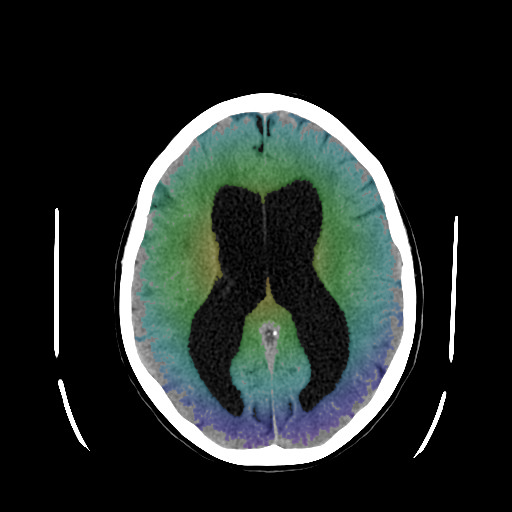

Υδροκέφαλος είναι η περίσσεια εγκεφαλονωτιαίου υγρού στο κεντρικό νευρικό σύστημα. Εγκεφαλονωτιαίο υγρό (Ε.Ν.Υ.) είναι το υγρό το οποίο περιβάλει το κεντρικό νευρικό σύστημα και εμπεριέχεται από τις μήνιγγες του εγκεφάλου. Το Ε.Ν.Υ. επίσης κυκλοφορεί στο εσωτερικό του εγκεφάλου, σε κοιλότητές του, οι οποίες ονομάζονται κοιλίες. Οποιαδήποτε αύξηση της παραγωγής, μείωση της απορρόφησης ή παρεμπόδιση της κυκλοφορίας του προς τα σημεία απορρόφησης δημιουργεί υδροκέφαλο. Ο υδροκέφαλος διαχωρίζεται σε αποφρακτικό (όταν αποφράσσεται η κυκλοφορία του Ε.Ν.Υ.) και επικοινωνούντα (όταν υπερπαράγεται ή, συχνότερα, δυσαπορροφάται το Ε.Ν.Υ.). Τα συμπτώματά του είναι, στην περίπτωση του αποφρακτικού υδροκέφαλου, κεφαλαλγία, ναυτία και έμετος, διαταραχή της όρασης, υπνηλία, λήθαργος κ.α., με ταχεία επιδείνωση. Η πρόγνωση είναι πολύ κακή και απαιτείται άμεση χειρουργική θεραπεία. Ο επικοινωνούν υδροκέφαλος έχει συμπτώματα τα οποία είναι συνήθως βραδύτερα αναπτυσσόμενα και συμπεριλαμβάνουν, πέραν των ανωτέρω, διαταραχές της μνήμης, αστάθεια βάδισης και ακράτεια ούρων, ειδικά στην υποκατηγορία του υδροκεφάλου φυσιολογικής πίεσης. Η θεραπεία είναι και εδώ κατά κανόνα χειρουργική. |

Η παραγωγή του Ε.Ν.Υ. γίνεται κατά το μεγαλύτερο μέρος σε αγγειακά πλέγματα στις κοιλίες του εγκεφάλου, τα χοριοειδή πλέγματα, και η απορρόφησή του στα πακχιόνεια σωμάτια στην επιφάνεια του εγκεφάλου από όπου αποχετεύεται στις μεγάλες φλέβες του εγκεφάλου. Ο συνολικός όγκος του Ε.Ν.Υ. στο κεντρικό νευρικό σύστημα είναι περίπου 150 ml και καθημερινά παράγονται περίπου 450-750 ml, δηλαδή ανακυκλώνεται 3-5 φορές ανά 24 ώρες. Οποιαδήποτε αύξηση της παραγωγής, μείωση της απορρόφησης ή παρεμπόδιση της κυκλοφορίας του προς τα σημεία απορρόφησης δημιουργεί υδροκέφαλο.

Υπάρχουν 2 βασικοί τύποι υδροκέφαλου: Ο υδροκέφαλος αποφρακτικού τύπου και ο υδροκέφαλος επικοινωνούντος τύπου. Ο υδροκέφαλος αποφρακτικού τύπου δημιουργείται όταν αποφραχθεί η κυκλοφορία του Ε.Ν.Υ. προς τα σημεία παροχέτευσής του, συνήθως από όγκους εγκεφάλου ή άλλες χωροκατακτητικές εξεργασίες. Αυτό προκαλεί διάταση του κοιλιακού συστήματος, αύξηση της ενδοκράνιας πίεσης (από την συσσώρευση εγκεφαλονωτιαίου υγρού στην ανένδοτη κρανιακή κοιλότητα) και πίεση στο εγκεφαλικό παρέγχυμα. Συγγενείς δυσπλασίες του κεντρικού νευρικού συστήματος, όπως η στένωση του υδραγωγού του Sylvius, οι δυσπλασίες Chiari I, II και Dandy Walker που προκαλούν επίσης αποφρακτικό υδροκέφαλο και πλήττουν συνήθως παιδιά και δεν θα αναπτυχθούν περαιτέρω σε αυτή την ενότητα. Ο υδροκέφαλος επικοινωνούντος τύπου δημιουργείται όταν υπερπαράγεται Ε.Ν.Υ.(όπως στην περίπτωση των σπάνιων όγκων του χοριοειδούς πλέγματος) ή, συχνότερα, όταν αυτό δυσαπορροφάται. Αυτό συμβαίνει μετά από λοιμώξεις ή αιμορραγίες στο κεντρικό νευρικό σύστημα και σε ορισμένους ηλικιωμένους χωρίς αποσαφηνισμένη αιτία (ιδιοπαθής). Υπολογίζεται ότι 1 % του πληθυσμού θα παρουσιάσει κάποια στιγμή υδροκέφαλο κάποιου τύπου.

Τα συμπτώματα του αποφρακτικού υδροκεφάλου είναι έντονη και επίμονος κεφαλαλγία με συνοδό ναυτία ή/και εμέτους, μείωση της οπτικής οξύτητας, πάρεση οφθαλμοκινητικών συζυγιών με διπλωπία, υπνηλία και λήθαργο. Η επιδείνωσή των συμπτωμάτων γίνεται γρήγορα και μπορεί να οδηγήσει σε κώμα και θάνατο. Ο υδροκέφαλος επικοινωνούντος τύπου έχει τα ίδια ουσιαστικά συμπτώματα με κάπως βραδύτερη εξέλιξη. Ο υδροκέφαλος φυσιολογικής πίεσης, μια πιο ήπια μορφή επικοινωνούντος υδροκεφάλου χαρακτηρίζεται από την τριάδα των παρακάτω συμπτωμάτων, σε διαφόρους βαθμούς έκαστο: διαταραχή βάδισης (αστάθεια), διαταραχή μνήμης και ακράτεια ούρων. Συγχέεται συχνά με την γεροντική ή προγεροντική άνοια (N.Alzheimer) και έχει αργή εξέλιξη.